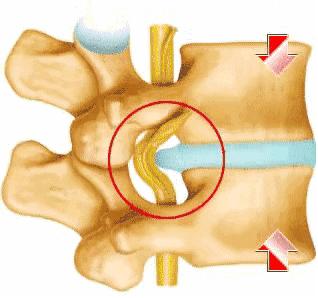

术前CT检查:L5/S1椎间盘突出,黄韧带肥厚。